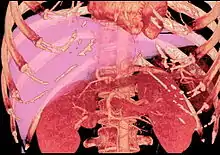

Technique

Before transplantation, liver-support therapy might be indicated (bridging-to-transplantation). Artificial liver support like liver dialysis or bioartificial liver support concepts are currently under preclinical and clinical evaluation. Virtually all liver transplants are done in an orthotopic fashion; that is, the native liver is removed and the new liver is placed in the same anatomic location.[7] The transplant operation can be conceptualized as consisting of the hepatectomy (liver removal) phase, the anhepatic (no liver) phase, and the postimplantation phase. The operation is done through a large incision in the upper abdomen. The hepatectomy involves division of all ligamentous attachments to the liver, as well as the common bile duct, hepatic artery, hepatic vein and portal vein. Usually, the retrohepatic portion of the inferior vena cava is removed along with the liver, although an alternative technique preserves the recipient's vena cava ("piggyback" technique).

The donor's blood in the liver will be replaced by an ice-cold organ storage solution, such as UW (Viaspan) or HTK until the allograft liver is implanted. Implantation involves anastomoses (connections) of the inferior vena cava, portal vein, and hepatic artery. After blood flow is restored to the new liver, the biliary (bile duct) anastomosis is constructed, either to the recipient's own bile duct or to the small intestine. The surgery usually takes between five and six hours, but may be longer or shorter due to the difficulty of the operation and the experience of the surgeon.

The large majority of liver transplants use the entire liver from a non-living donor for the transplant, particularly for adult recipients. A major advance in pediatric liver transplantation was the development of reduced size liver transplantation, in which a portion of an adult liver is used for an infant or small child. Further developments in this area included split liver transplantation, in which one liver is used for transplants for two recipients, and living donor liver transplantation, in which a portion of a healthy person's liver is removed and used as the allograft. Living donor liver transplantation for pediatric recipients involves removal of approximately 20% of the liver (Couinaud segments 2 and 3).